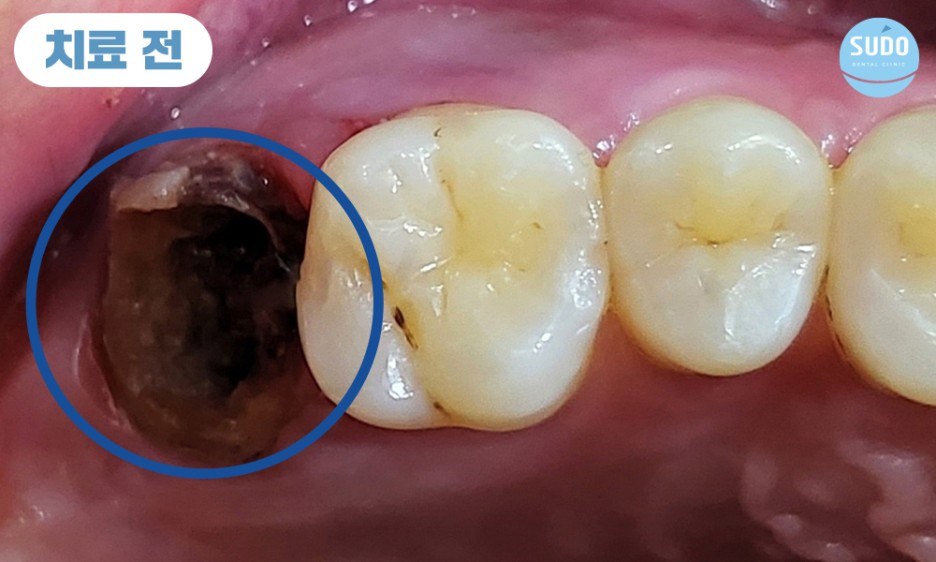

기존의 보철물 제거하고 보니, 이미 뿌리까지 충치가 많이 진행된 상태로 살려서 쓰기 힘들 것이라 판단되어 당일 발치 후 임플란트 진행 계획을 수립하였습니다.

이전 진료 당시에 신경치료를 완료한 후 보철물을 부착한 상태였으므로 충치가 심하게 진행되었음에도 통증을 전혀 느낄 수 없었습니다.